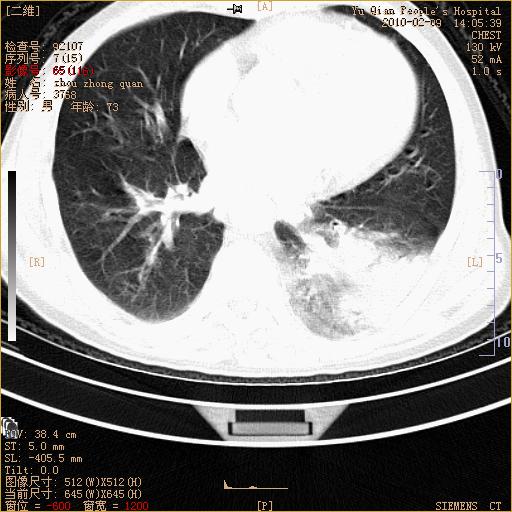

男性,73岁,咳嗽咳血数天,诊为肺ca伴左肺下叶后段阻塞性炎症、肺不张妥否?

右下肺有转移?

左下肺中央型肺癌伴结段形肺不张,左侧胸腔积液,纵隔内见部分增大淋巴结(反应性增生或转移)

左下基底干支气管明显变窄。

左肺下叶基底段支气管狭窄,左肺门增大,左肺下叶团片状病灶。中心型肺癌伴柱塞性炎症可能大,建议支气管镜检查。

左下肺中央型肺癌伴节段性肺不张,左侧胸腔积液,纵隔内见肿大淋巴结

左下基底段支气管变窄。建议进一步纤支镜检查。

1、左肺下叶后基地段肺癌伴阻塞性炎症,左下肺门淋巴结转移。2、左侧胸腔积液。